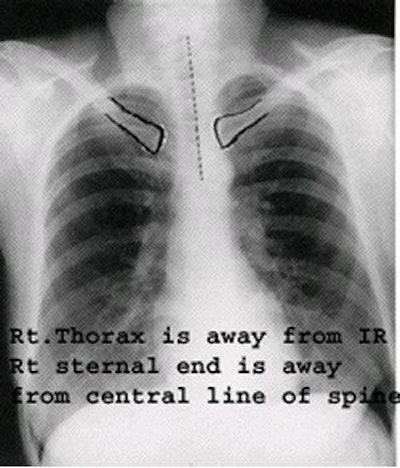

Rotation

Even a small degree of rotation distorts the mediastinal borders, and the lung nearest the film will appear less translucent. The following points should be stressed to obtain a true PA view (without rotation):

PA view with rotation. Image courtesy of Dr. Naveed Ahmad.

- Ensure that the patient is standing evenly on both feet.

- Both shoulders should be rolled forward and downward.

- The chest radiograph should be well-centered so that the medial ends of the clavicle are equidistant from the vertebral spinous processes at T4/5. However, scoliosis and other thoracic deformities negate the value of conventional centering.

- No rotation. Rotation on a PA chest radiograph can be determined by examining both sternal ends of the clavicles for a symmetric appearance in relationship to the spine. On a true PA chest without any rotation, both the right and left sternal ends of the clavicle will be the same distance from the center line of the spine. The direction of rotation can be determined by which sternal end of the clavicle is closest to the spine.